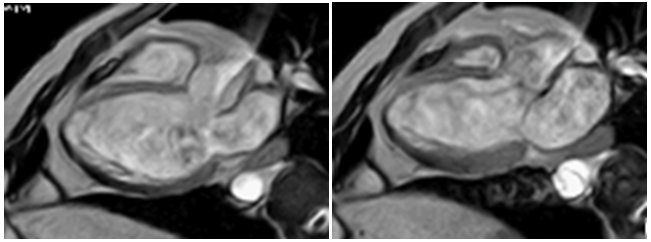

Dilated cardiomyopathy and LVNC: poor outcome?: 3-months-old patient with dilated cardiomyopathy and severe impairment of left ventricular function. Ventricular dilation observed on echocardiogram with prominent left ventricular hypertrabeculation, fulfilling the criteria of LVNC. The poor performance and the difficult clinical management prompted physicians to perform a CMR to evaluate myocarditis and/or LVNC. CMR was performed under general anesthesia and Gadolinium-DTPA contrast. Hypertrabeculation observed in the left ventricle involved the anterior and lateral wall in the middle and apical segments with severely impaired ejection fraction (Figure 5).

Figure 5 Image of fast field echo (gradient image) CMR short axis of both ventricles, left image in diastole and right image at systole. There is little change in volume in both ventricles due deteriorated ventricular function. Hypertrabeculation of both ventricles is evident.